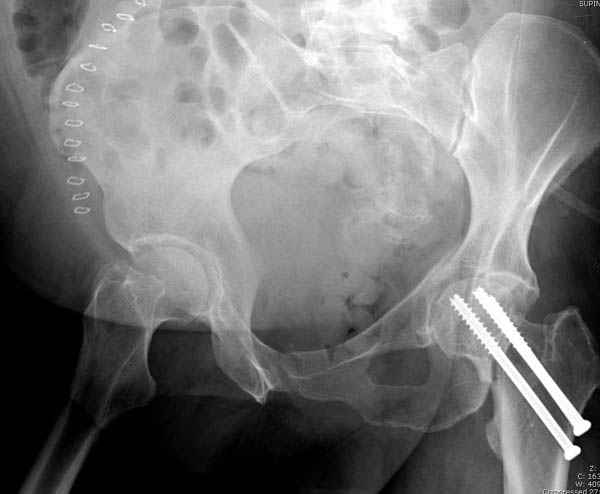

Уважаемые коллеги! С прошедшеми Вас праздниками. Теперь ближе к трудовым будням. Поступила 16 летняя девушка неделю назад. Механизм травмы падение с 5 этажа. Краткий диагноз:закрытый перелом левой ключицы, левого плеча, закрытый вертикально и ротационно нестабильный перелом костей таза:закрытый перелом левой подвздошной кости, переломы лонной кости справа, перелом обоих колонн вертлужной впадины слева;субкапитальный перелом шейки левой бедренной кости со смещением. По тактике лечения таза возникли следующие вопросы: 1. С чего начать - фиксации переломов вертлужной впадины или устранения деформаций таза? 2. Надо ли фиксировать шейку или фиксировать бедро в аппарате вместе с тазом, а после сращения таза планировать ТЭП ТБС? Если имеются еще какие подводные камни, будем рады выслушать.Спасибо.

В положении на спине подвздошным и надлобковым доступом восстанавливается тазовое кольцо, фиксация пластинами. При хорошей репозиции может улучшиться конгруэнтность в суставе.

Затем, если положение хорошее, закрытый остеосинтез шейки винтами.

Если нет - в положении на боку, синтез задней колонны из наружно-латерального доступа и синтез головки винтами, но уже под визуальным контролем.